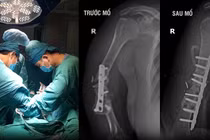

Khớp giả là tình trạng xương không liền sau phẫu thuật. Điều trị khớp giả là một quá trình khó khăn, phức tạp và lâu dài.